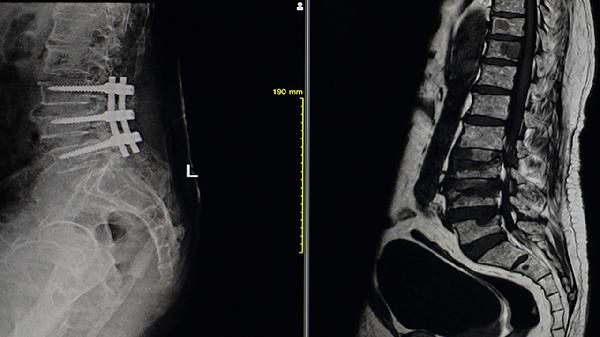

全髖關(guān)節(jié)置換術(shù)適用于嚴(yán)重髖關(guān)節(jié)強(qiáng)直患者,可恢復(fù)活動(dòng)功能。脊柱矯形術(shù)針對(duì)駝背畸形,需評(píng)估心肺功能后實(shí)施。微創(chuàng)椎間孔鏡手術(shù)能解除神經(jīng)壓迫,術(shù)后需配合康復(fù)訓(xùn)練。手術(shù)風(fēng)險(xiǎn)包括感染、假體松動(dòng)等,需嚴(yán)格掌握適應(yīng)證。